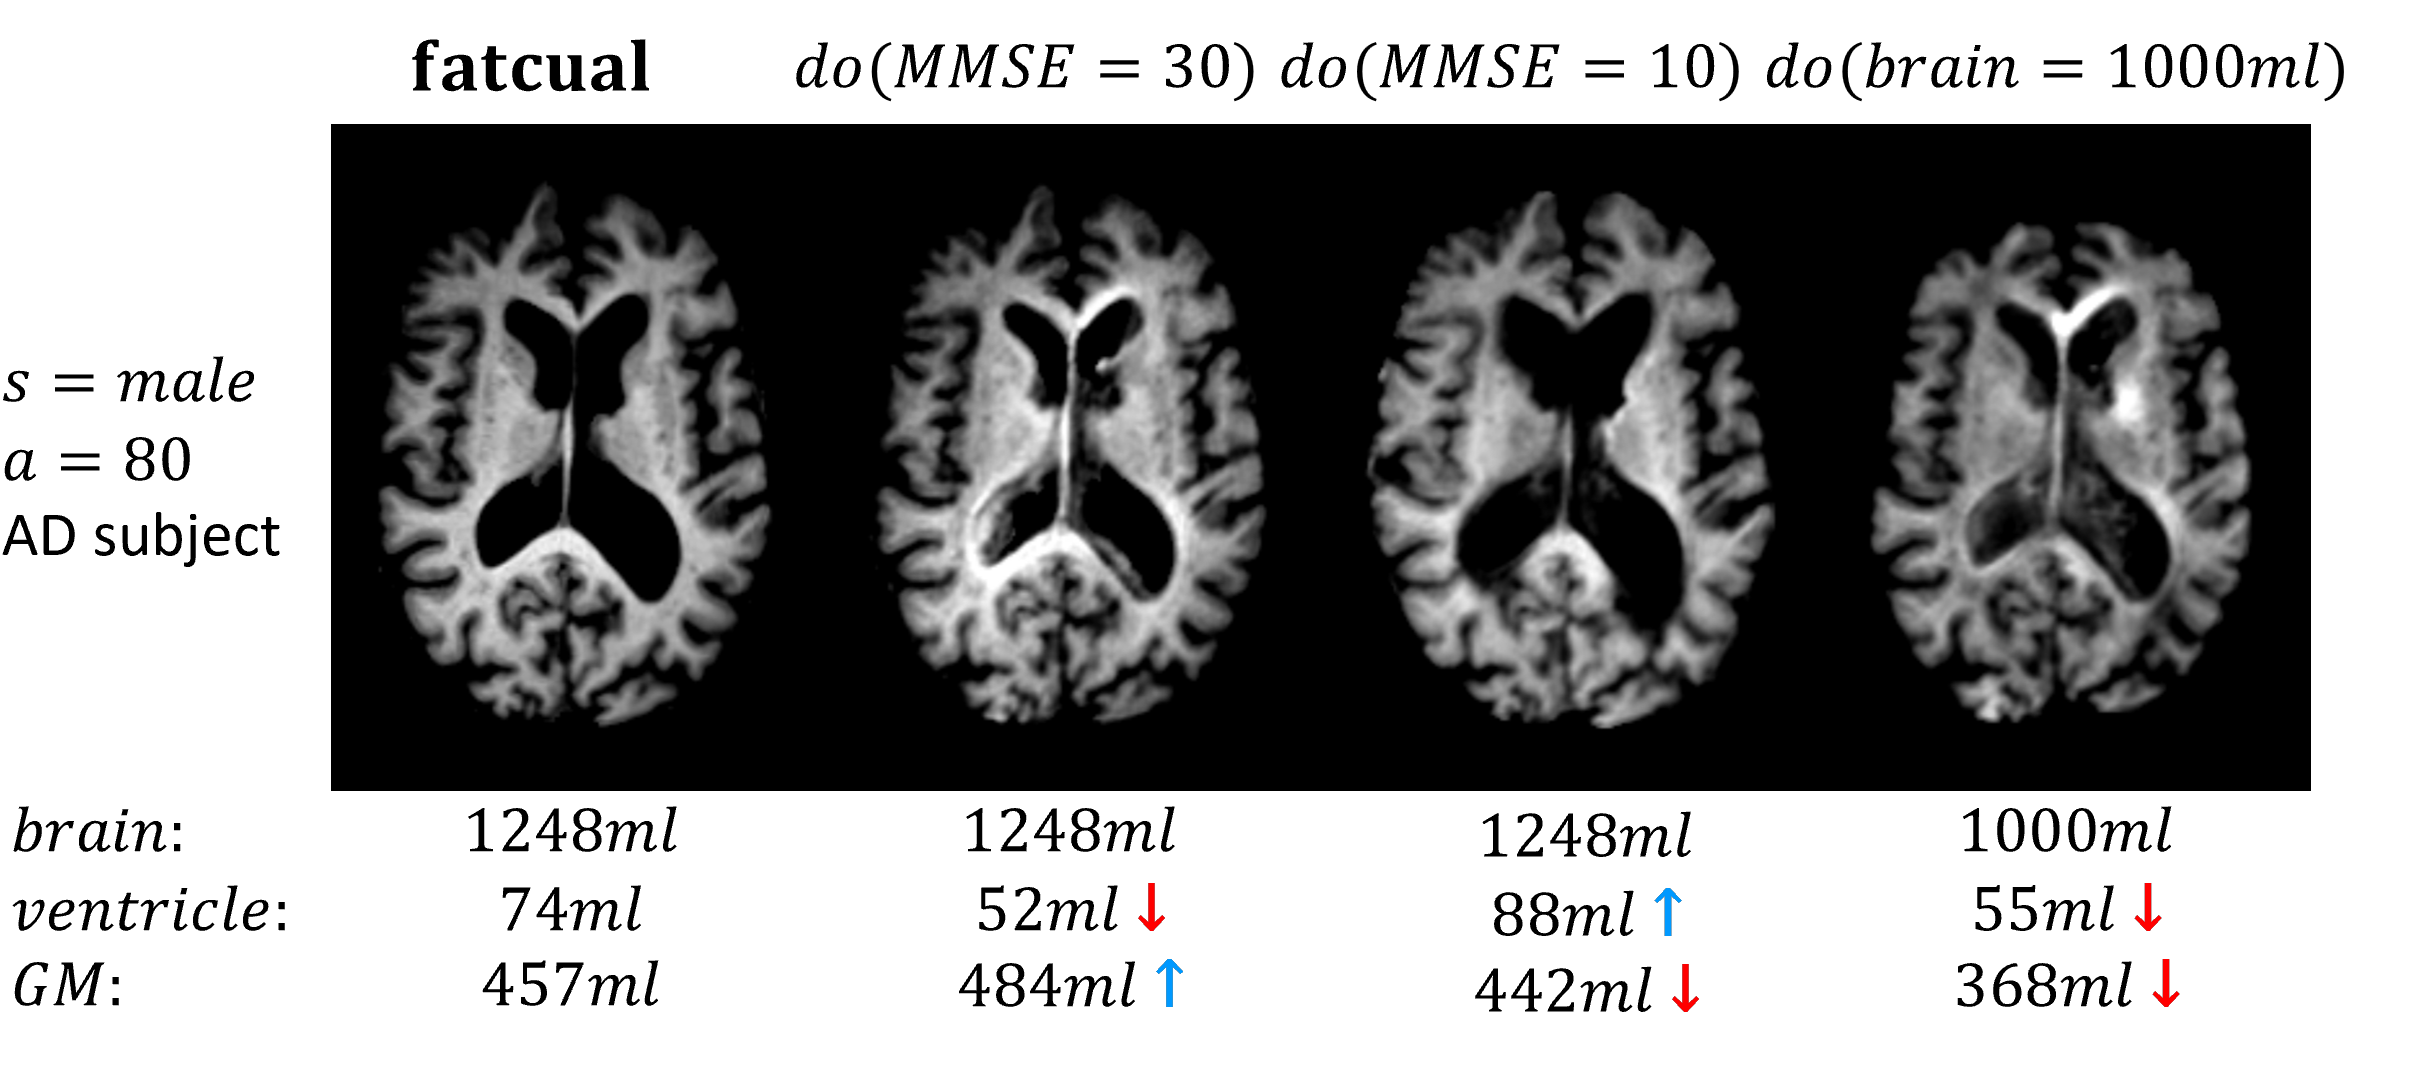

We choose Alzheimer’s Disease (AD) as the scenario. AD is the most common type of dementia and involves the atrophy of brain, which can be reflected in MR images. Besides, the causality in AD is of plenty of research which can provide our model with prior knowledge. We manage to synthesize brain MRI in 3D while handling the causal relationships between demographic variables, clinical disease variables and MR images. This model makes it possible to (i) sample and generate controllable life-like 3D brain MR images and (ii) answer the aforementioned counterfactual questions based on existing images. Fig. 1(b) shows the synthesised counterfactual MRI in the situation of the subject without AD or with a smaller brain, which contradicts with the fact.

(b) counterfactual MRI

Figure 1: (a) The causal graph for MRI for AD. Variables are image (i𝑖i), age (a𝑎a), sex (s𝑠s), Mini Mental Sate Examination(MMSE) score (m𝑚m) and brain (b𝑏b), ventricle (v𝑣v) , grey matter (g𝑔g) volumes. (b) The counterfactual MRI results, set score and brain volume.

As Table 3 shows, the brain volume changes most accurately possibly because brain is the largest (average 1354ml1354𝑚𝑙1354ml) compared with grey matter (527ml527𝑚𝑙527ml) and ventricle (41ml41𝑚𝑙41ml). SSIM between 2 random real images is 0.71(.001) and the SSIM between 2 images of the same individual (interval >> 1 year) is 0.85(.05), which proves that counterfactual MRI preserves the characteristic structure. Figure 1(b) visualizes counterfactual MR images. We set MMSE = 30 for an AD patient to answer the question What would the brain image look like if the subject did not have Alzheimer’s Disease? Results show a smaller ventricle and a larger grey matter volume, in accordance with the medical research on AD [30, 31]. We also show how the image would look like if the illness is more severe (MMSE = 10) or if the subject has a smaller brain (brain volume = 1000ml). See more results in supplementary material.